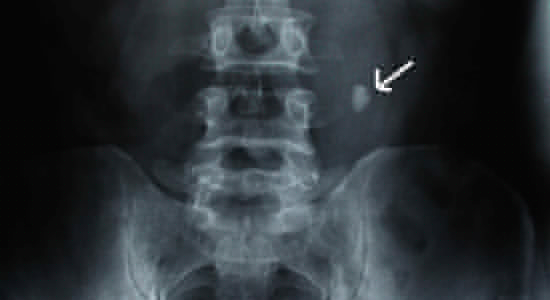

Камень в мочеточнике при рентгенографии

Инструментальные методы исследования позволяют определить размеры, форму конкрементов, места их локализации и визуально оценить состояние почек. Среди инструментальных методов диагностики широко распространены:

- рентгенография;

- обзорная и экскреторная урография;